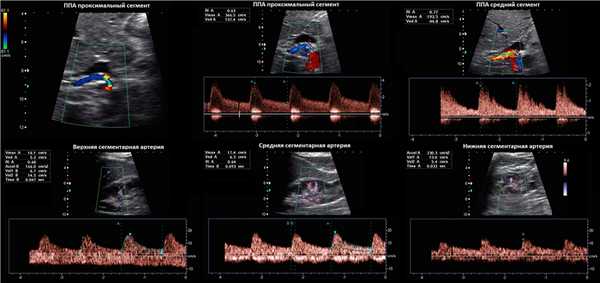

Рисунок. Пациентка 60-ти лет с рефрактерной артериальной гипертензией. PSV на брюшной аорте 59 см/сек. В проксимальном отделе ППА при ЦДК элайзинг (1), PSV значительно повышен 366 см/сек (2), RAR 6,2. В среднем сегменте ППА при ЦДК элайзинг, PSV 193 см/сек (3), RAR 3,2. На сегментарных артериях без существенного увеличения времени ускорения: верхняя — 47 мс, средняя — 93 мс, нижняя — 33 мс. Заключение: Стеноз в проксимальном отделе правой почечной артерии.

Рисунок. Пациент с артериальной гипертензией. PSV в аорте 88,6 см/сек (1). В проксимальном отделе ППА элайзинг, PSV 452 см/сек, RAR 5,1 (2). В среднем отделе ППА элайзинг, PSV 385 см/сек, RAR 4,3 (3). В дистальном отделе ППА PSV 83 см/сек (4). На внутрипочечных сосудах tardus-parvus эффект не определяется, справа RI 0,62 (5), слева RI 0,71 (6), разница 0,09. Заключение: Стеноз в проксимальном отделе правой почечной артерии.